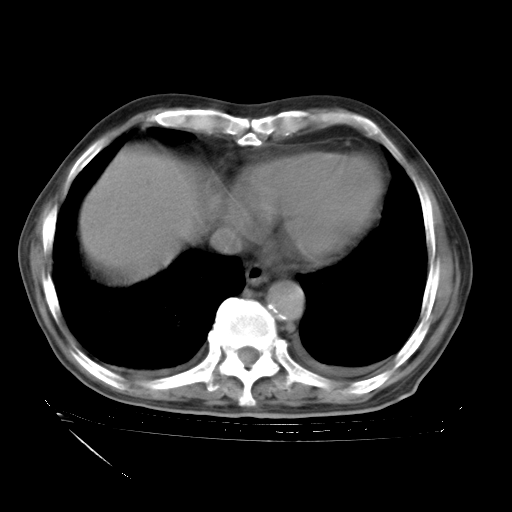

经过24天治疗,岳父的病情基本稳定。生活基本可以自理,可以下床活动。呼吸困难早已消失。体温基本正常。

只是甲强龙用80mg时血小板升到正常,改为60mg后又降到63×10*9/L。

主要治疗甲强龙80mg×14天,60mg×10天;同时抗结核(异烟肼+利福平+乙胺丁醇)。环磷酰胺0.1 tid 10天。

特别感谢胡教授、高管、桃子版主给出关键的治疗建议。桃版把所有肺部影像和全部临床资料请所在医院呼吸科、感染病科、结核科、临床免疫科专家会诊。临床免疫科专家制定了完整的治疗方案。